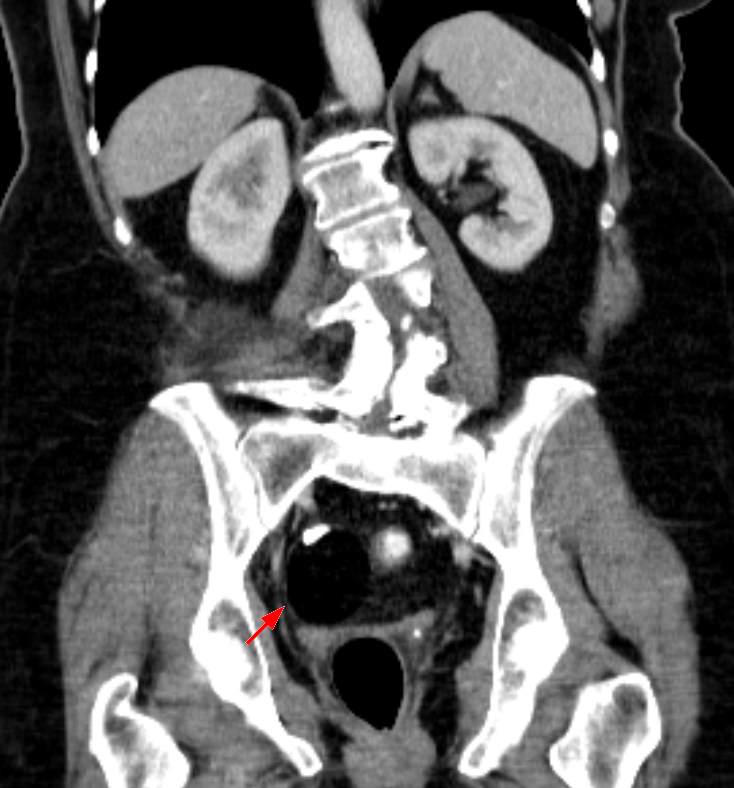

其实,人类生殖细胞已经有过自发发育的例子,然而这只能形成肿瘤,也就是畸胎瘤,男性发于睾丸,女性发于卵巢。

图为 卵巢畸胎瘤

在卵巢畸胎瘤中,可以看到类似正常的器官组织,比如毛发、软骨,甚至还有高度分化的眼、肢体等,但不太可能生产完整的器官。